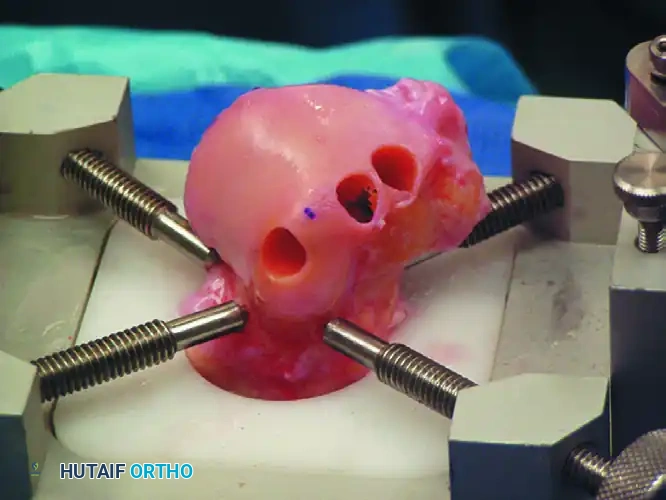

Arthroscopic retrograde drilling and bone grafting as described by Stone and Gould. (A) A guide pin is placed through the sinus tarsi using a modified ligament guide. (B) Graft material is compressed into the channel.

4. Decompression and Grafting: The tract is over-drilled. The cystic contents are curetted. To prevent articular collapse, the void is backfilled. Options include cancellous autograft, surgical-grade calcium sulfate, or bone marrow aspirate concentrate (BMAC) harvested from the iliac crest.